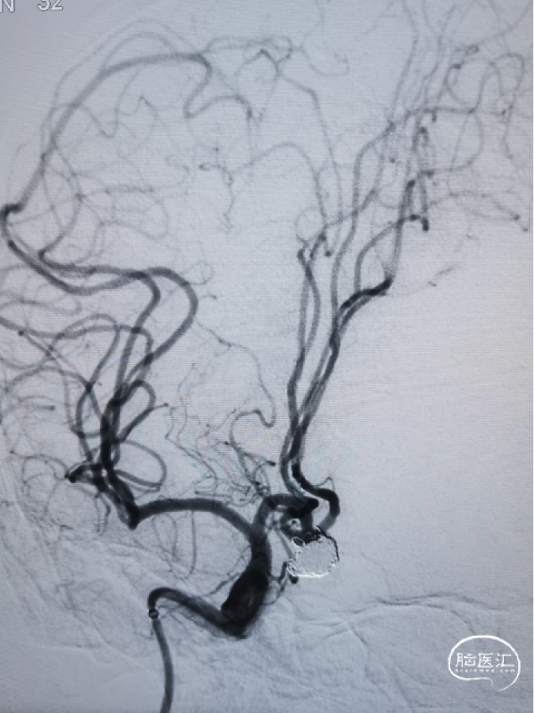

造影示“T”型支架左侧Atlas支架 3mm*15mm 、右侧 Atlas支架 4mm*21mm,动脉瘤致密栓塞,不显影。双侧A2段显影良好。

造影显示:右侧Acom宽颈动脉瘤,大小约为7.5mm×10.5mm,动脉瘤底有双侧凸起,动脉瘤瘤颈宽,双侧A2段自动脉瘤侧壁发出。右侧A2起始直径1.7mm,左侧A2段起始部直径1.4mm。BOT试验显示左侧A1段不显影。